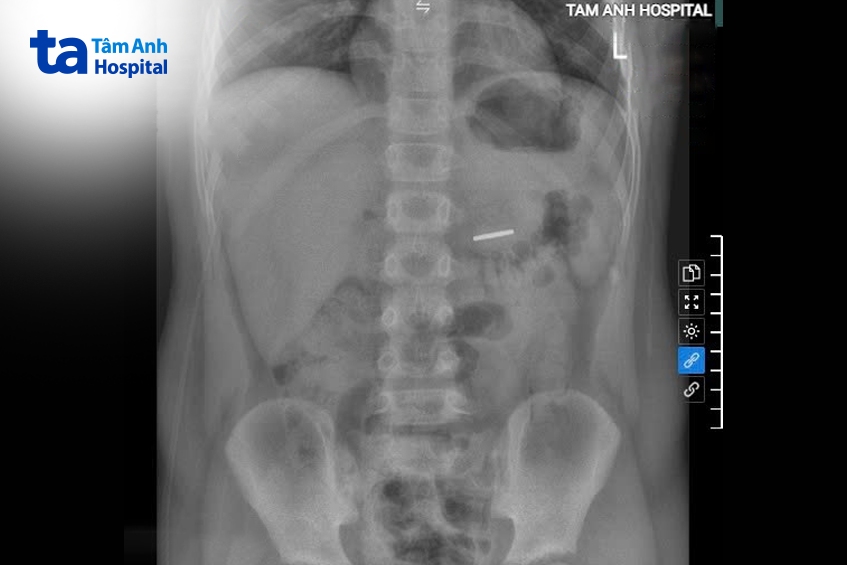

Khi được đưa vào Bệnh viện Đa khoa Tâm Anh Hà Nội, bé Cường tỉnh táo, tiếp xúc tốt, tim phổi bình thường, bụng mềm, không chướng, không có điểm đau bất thường. Kết quả chụp X-quang cho thấy có hình ảnh dị vật cản quang kích thước 2,5 cm nằm trong dạ dày.

Bác sĩ chỉ định nội soi dạ dày – tá tràng, lấy ra một thỏi nam châm vĩnh cửu màu nâu sẫm tại vị trí tá tràng D3. Sau can thiệp, bé Cường tỉnh táo, không có triệu chứng bất thường, xuất viện sau một ngày.